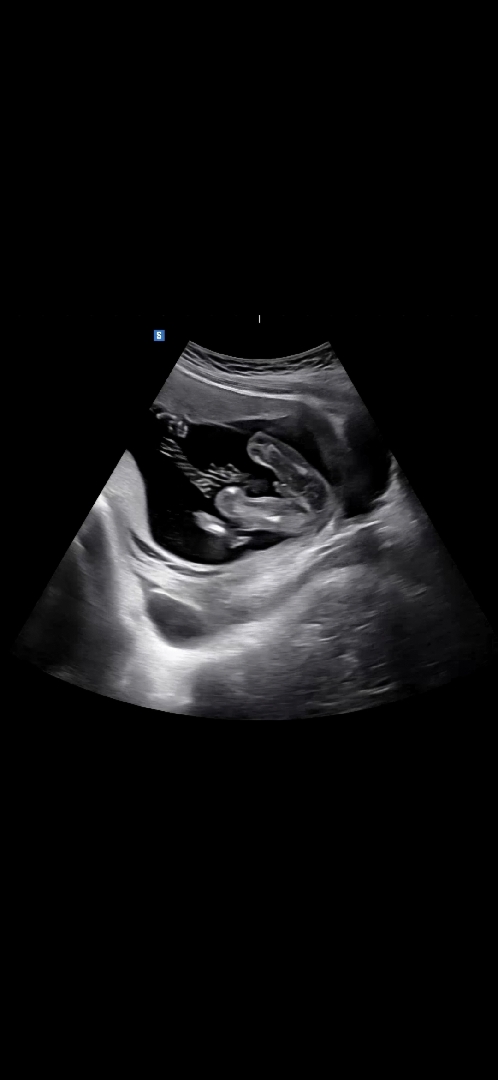

16주차 +4일 초음파 성별 봐주세요~

16주 4일차 초음파로 의사쌤이 처음으로 성별 말씀해주셨어요! 아들 같네요~ 하고 지나가셨는데 어떻게들 보이세요?ㅎㅎ 초음파로 성별반전이 있다고들하니 궁금해요

뒷구르기 하며 봐도 아들이네요♥️

10000프로 아들요 ^^